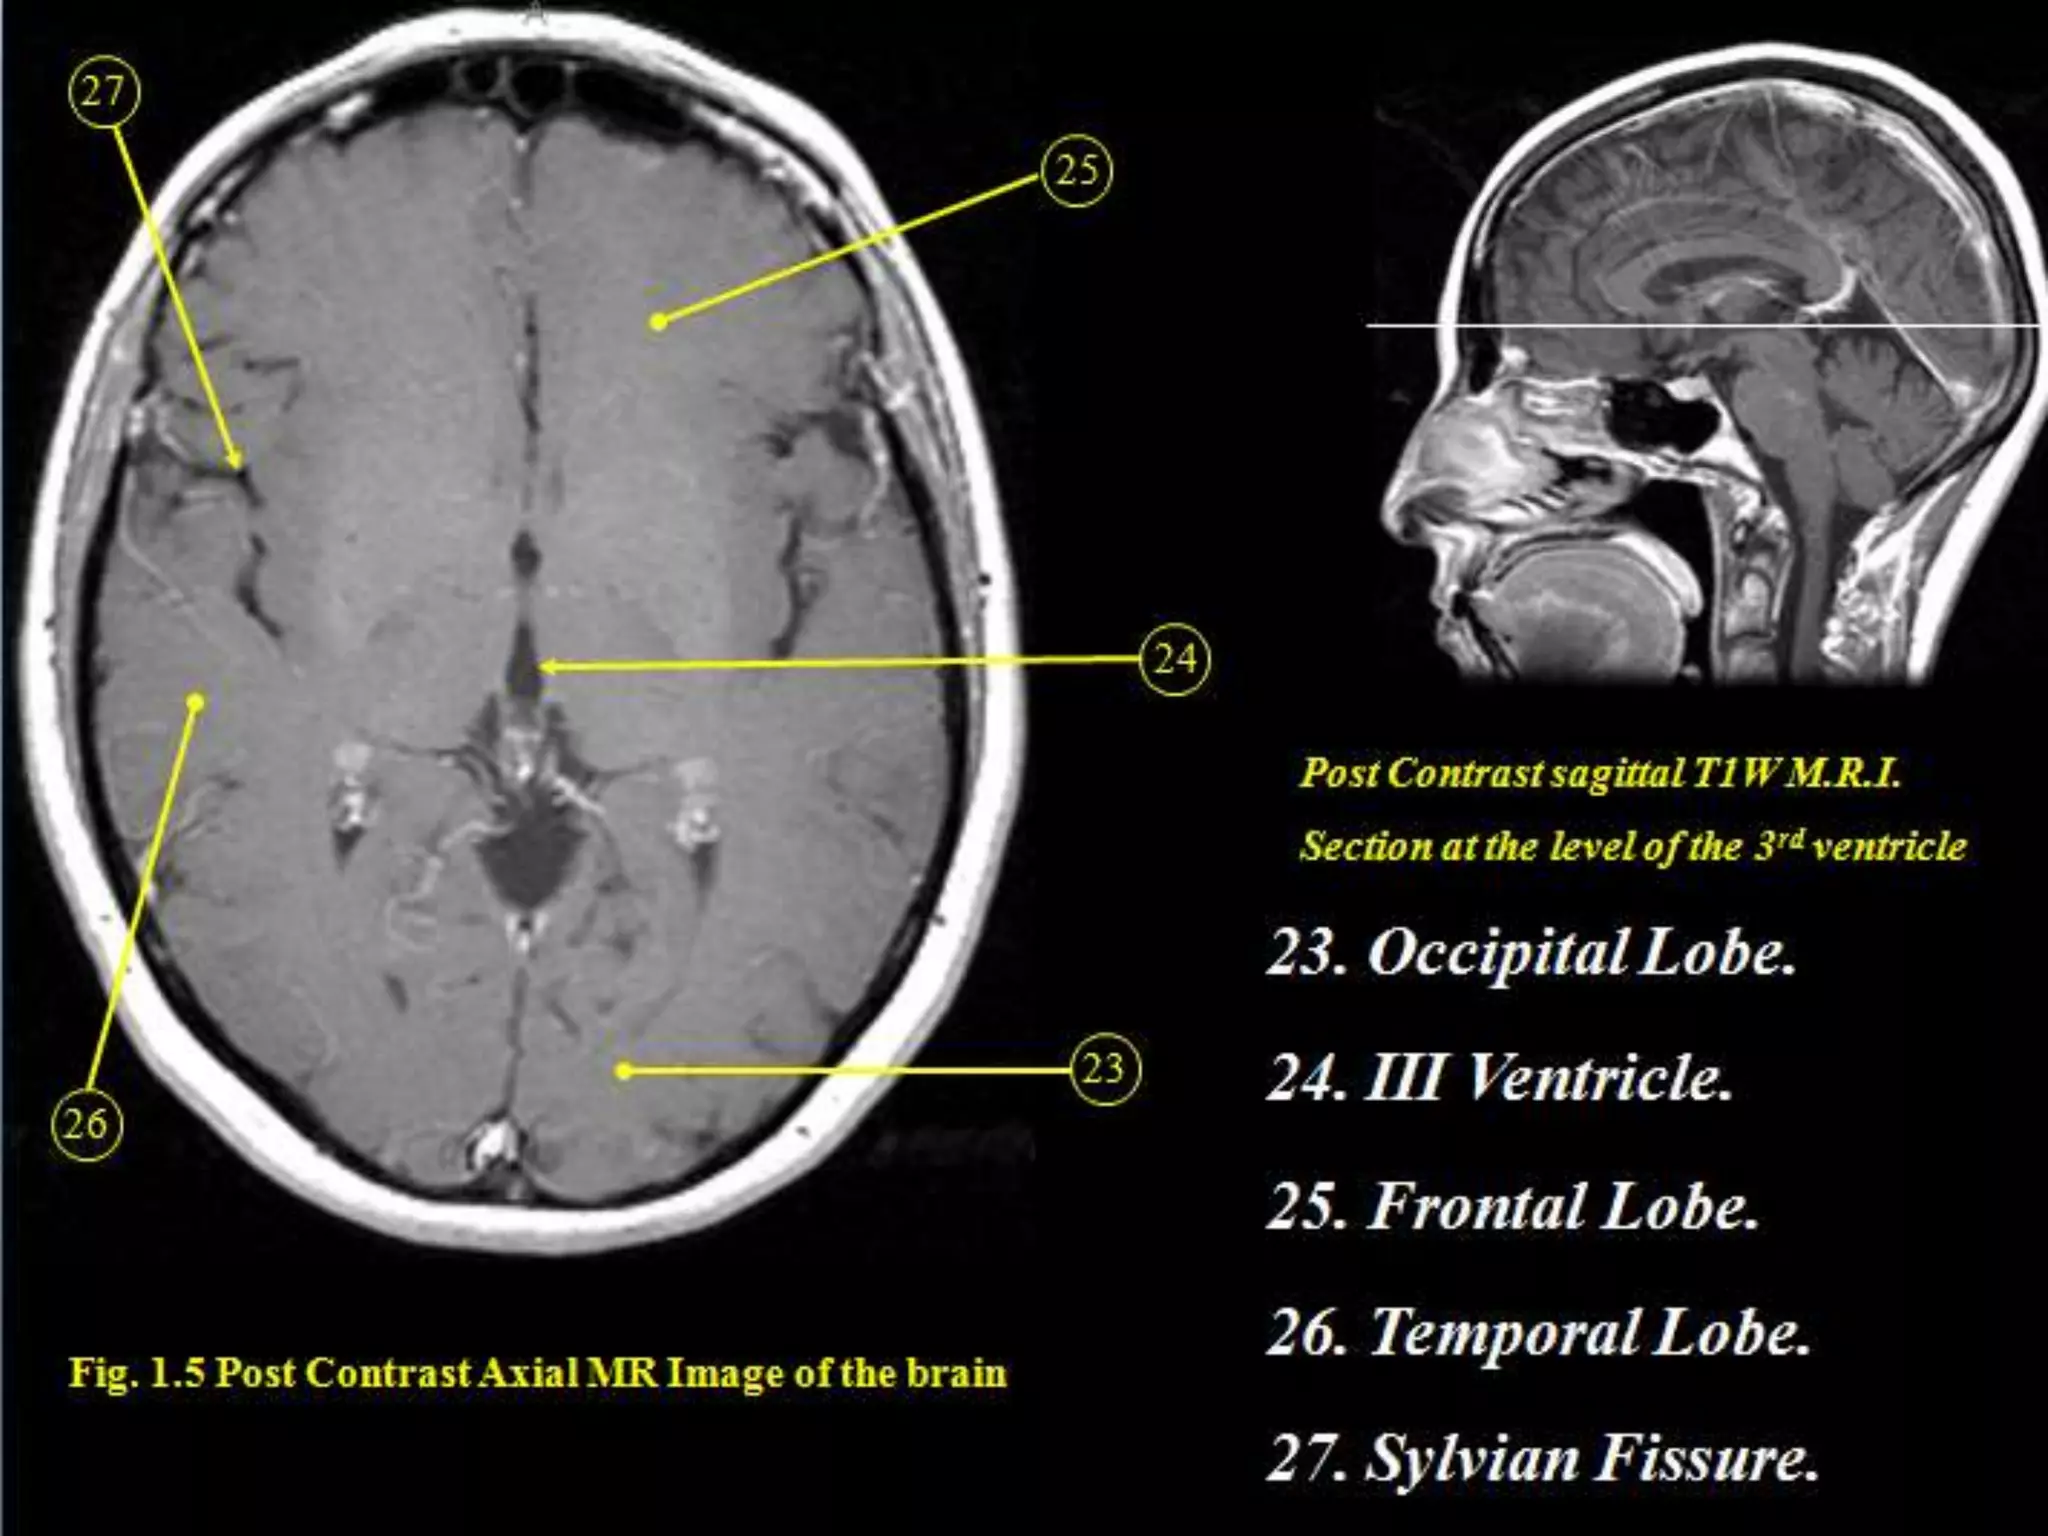

Sectional Anatomy: NormalAxial CT and MRI Anatomy. On CT and MR scans, the brain has been briefly viewed in infratentorial and supratentorial sections, as described below. CT scans are performed with a 15- to 20-degree angulation to the canthomeatal line at 8-mm increments. MRI scans are generally obtained parallel to the AC-PC line in the axial plane with 6-mm slice thickness. Using the sagittal view, the coronal sections are acquired parallel to the brain stem, and the sagittal sections are obtained perpendicular to the axial section. On MRI studies, cranial nerves IX and X can be demonstrated at this level because they emerge from the postolivary sulcus. The posterior aspect of the cerebellar hemispheres is outlined by the inferior portion of the cisterna magna.